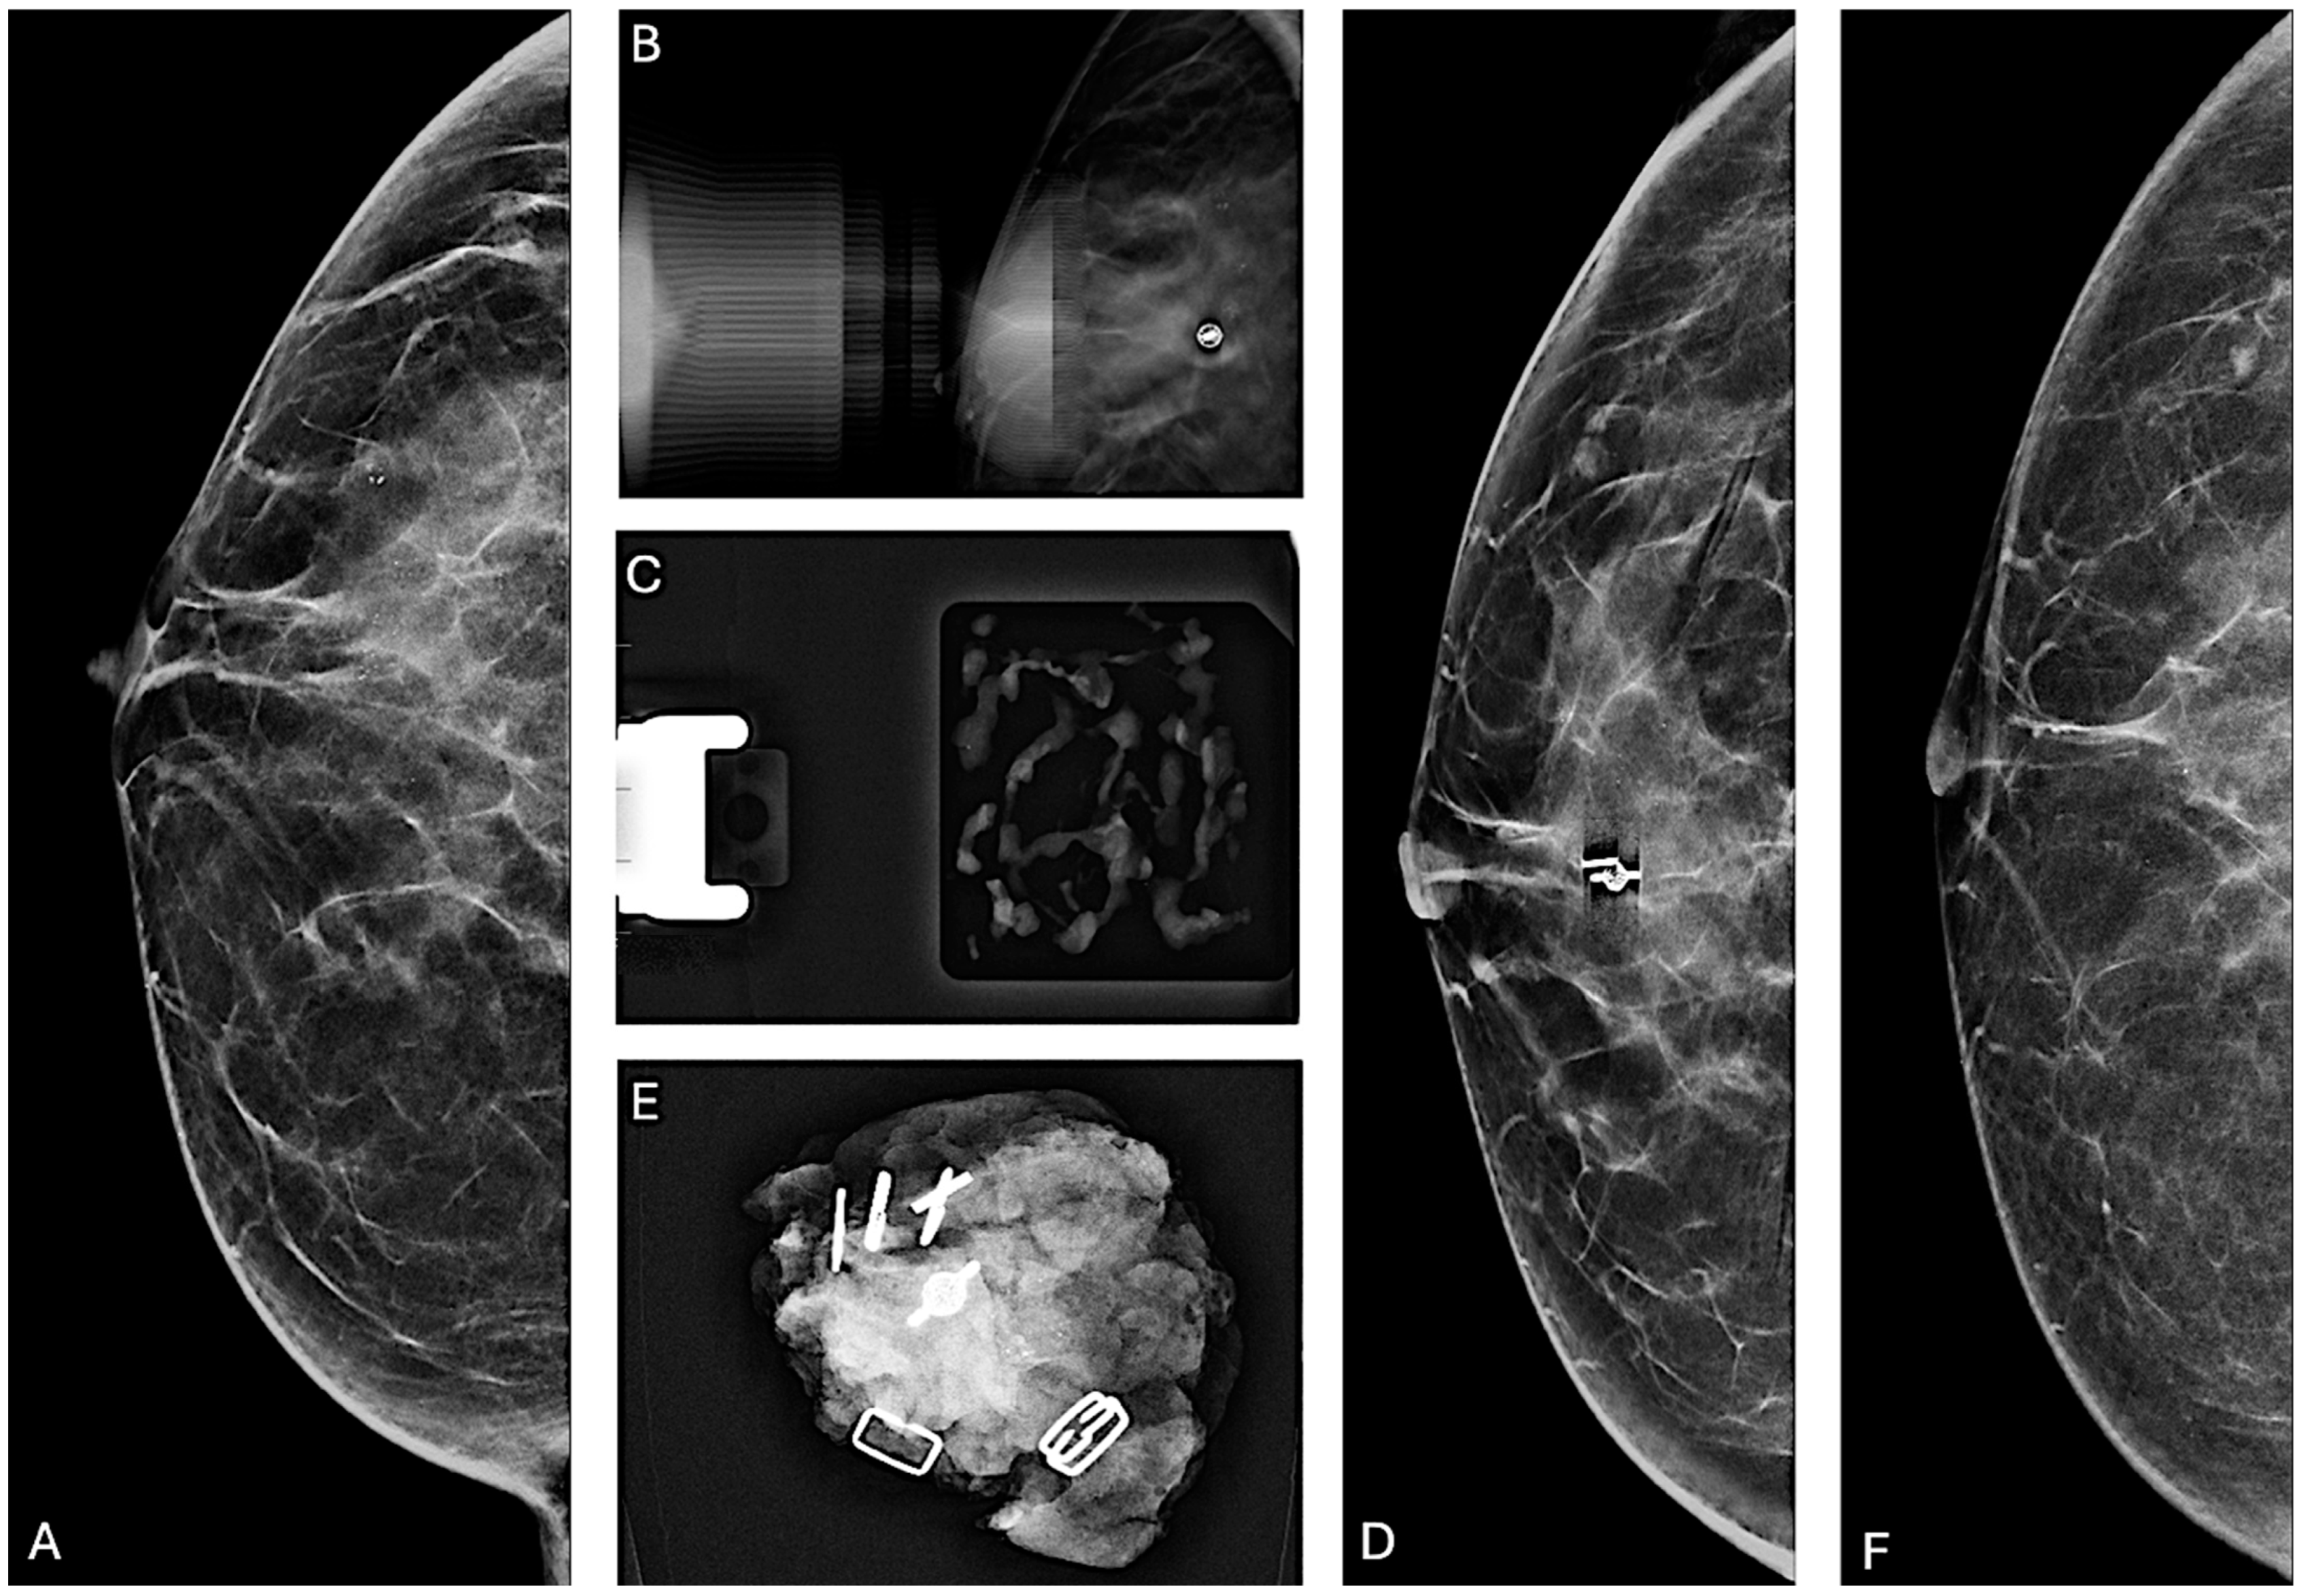

2.2. Stereotactic VABB

3.2. Microcalcification Removal